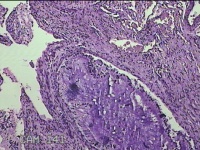

性别

女

年龄

31岁

临床诊断

宫颈上皮内瘤变

一般病史

发现宫颈CIN2 2个月。

标本名称

宫颈组织

大体所见

灰白暗红色组织2.8x1.8x0.3cm一块,表面糜烂,切面灰白暗红色,质软。

所提供图片不具有诊断价值。